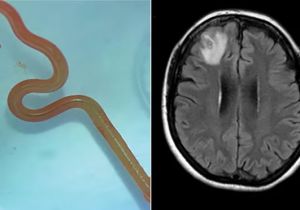

Oh My God! महिला के दिमाग में मिला 8 सेमी का जिंदा कीड़ा, डॉक्टर बोले- करियर का पहला हैरान करने वाला केस

29 Aug, 2023 03:58 PM IST | ASIAVARTANEWS.COMऑस्ट्रेलिया ऑस्ट्रेलिया में एक महिला के दिमाग में जिंदा कीड़ा मिलने का हैरान कर देने वाला...